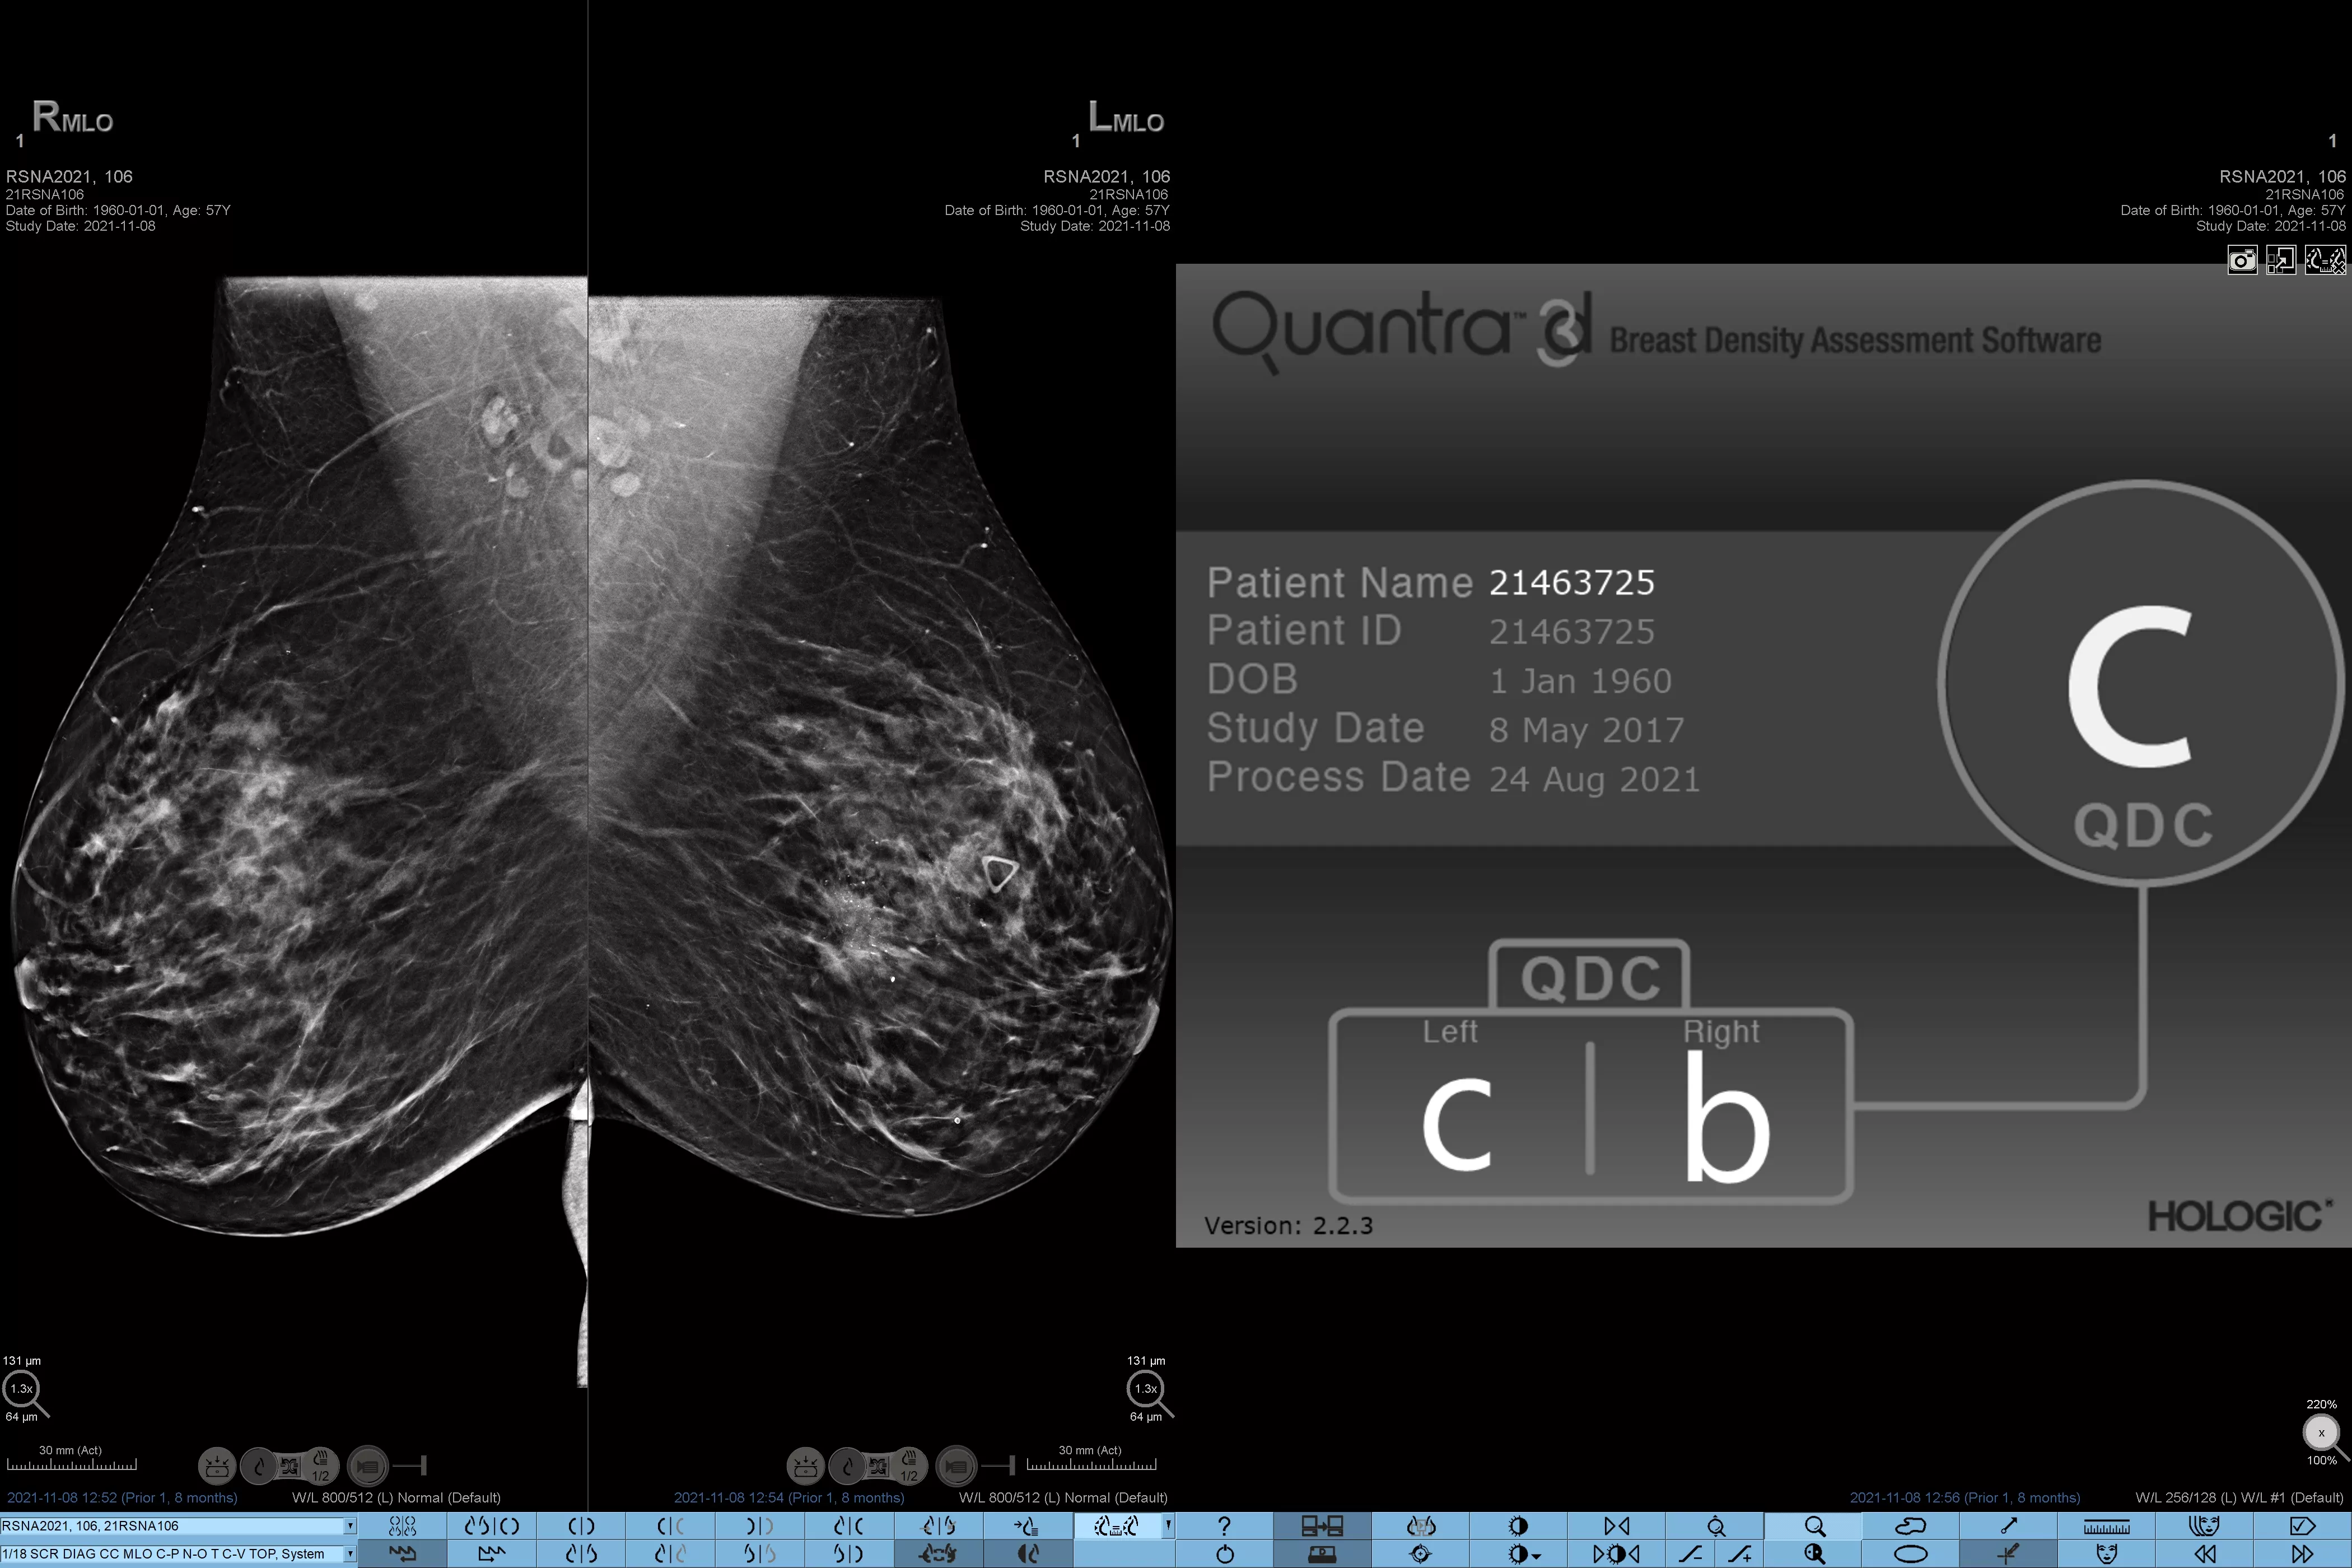

Man ved, at højere brysttæthed øger en kvindes risiko for brystkræft.1 Behovet for nøjagtige, objektive analyser er derfor afgørende. Quantra-teknologisoftwaren er drevet af maskinlæring og analyserer både 2D™ og tomosyntesebilleder for fordeling og tekstur af parenkymvæv. Den kategoriserer bryster i fire brystkompositionskategorier i overensstemmelse med vejledningen fra American College of Radiology (ACR) BI-RADS Atlas 5th Edition.2

* Scorer er baseret på ACR BI-RADS-kategorier på linje med den reviderede vejledning fra American College of Radiation (ACR) BI-RADS Atlas 5th Edition. Dette tager højde for mønster og tekstur i sammenlignet med volumen, når man bestemmer tæthed.

8. Breast composition categories as described in ACR BI-RADS Atlas.